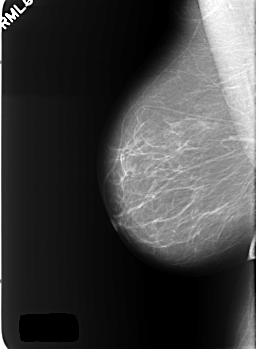

C_0401_1.RIGHT_MLO

RIGHT_MLO LINES 5576 PIXELS_PER_LINE 4152 BITS_PER_PIXEL 12 RESOLUTION 50 NON_OVERLAY